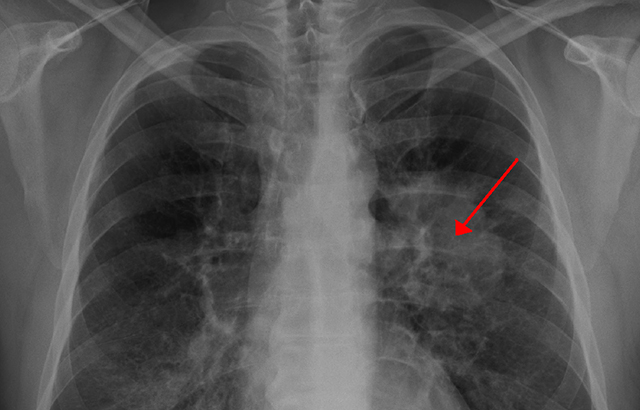

UKLS is the first and only lung cancer screening trial to take place in the UK and has provided in-depth information on how to set up a national lung cancer screening programme and identify high risk individuals in the population. It was a randomised controlled trial in 4,055 individuals and used special x-ray equipment to create detailed pictures of areas inside the patients’ bodies.